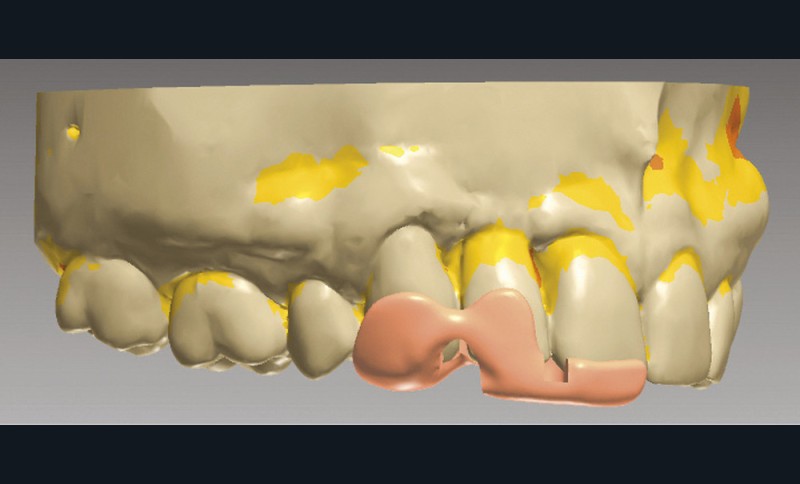

La situation clinique est transférée au prothésiste au moyen d’empreintes optiques (Trios 2, 3Shape) pour une conception numérique de la prothèse (fig. 8 et 9).

Une fois les modèles virtuels créés, l’armature du bridge est modélisée par Conception Assistée par Ordinateur sur le logiciel Trios Design Studio (3Shape) (fig. 10). La surface de connexion mesurée est de 9,8 mm2 (fig. 11) et celle de collage de 40,56 mm2, respectant ainsi les recommandations de la littérature [24].